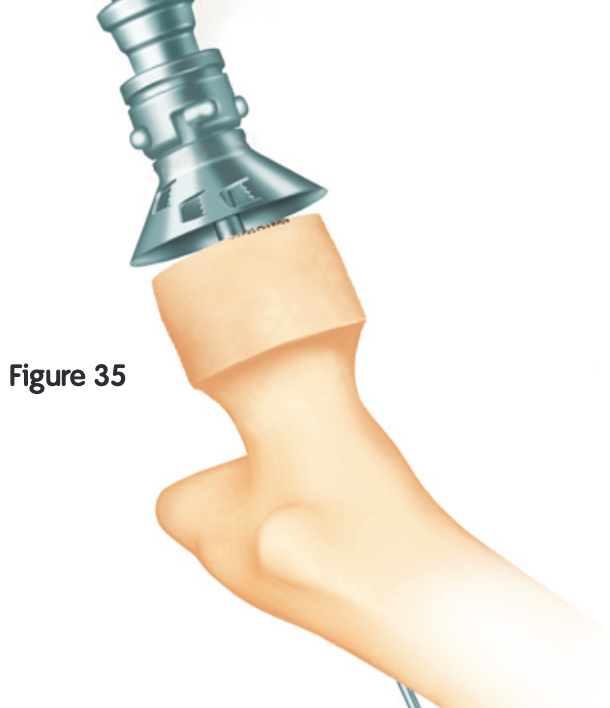

Femur - removal of femoral head cartilage and resurfacing with metal

Technique

Techniques

Birmingham Resurfacing

Smith&Nephew Birmingham Resurfacing PDF

Technical issues

Oversized head